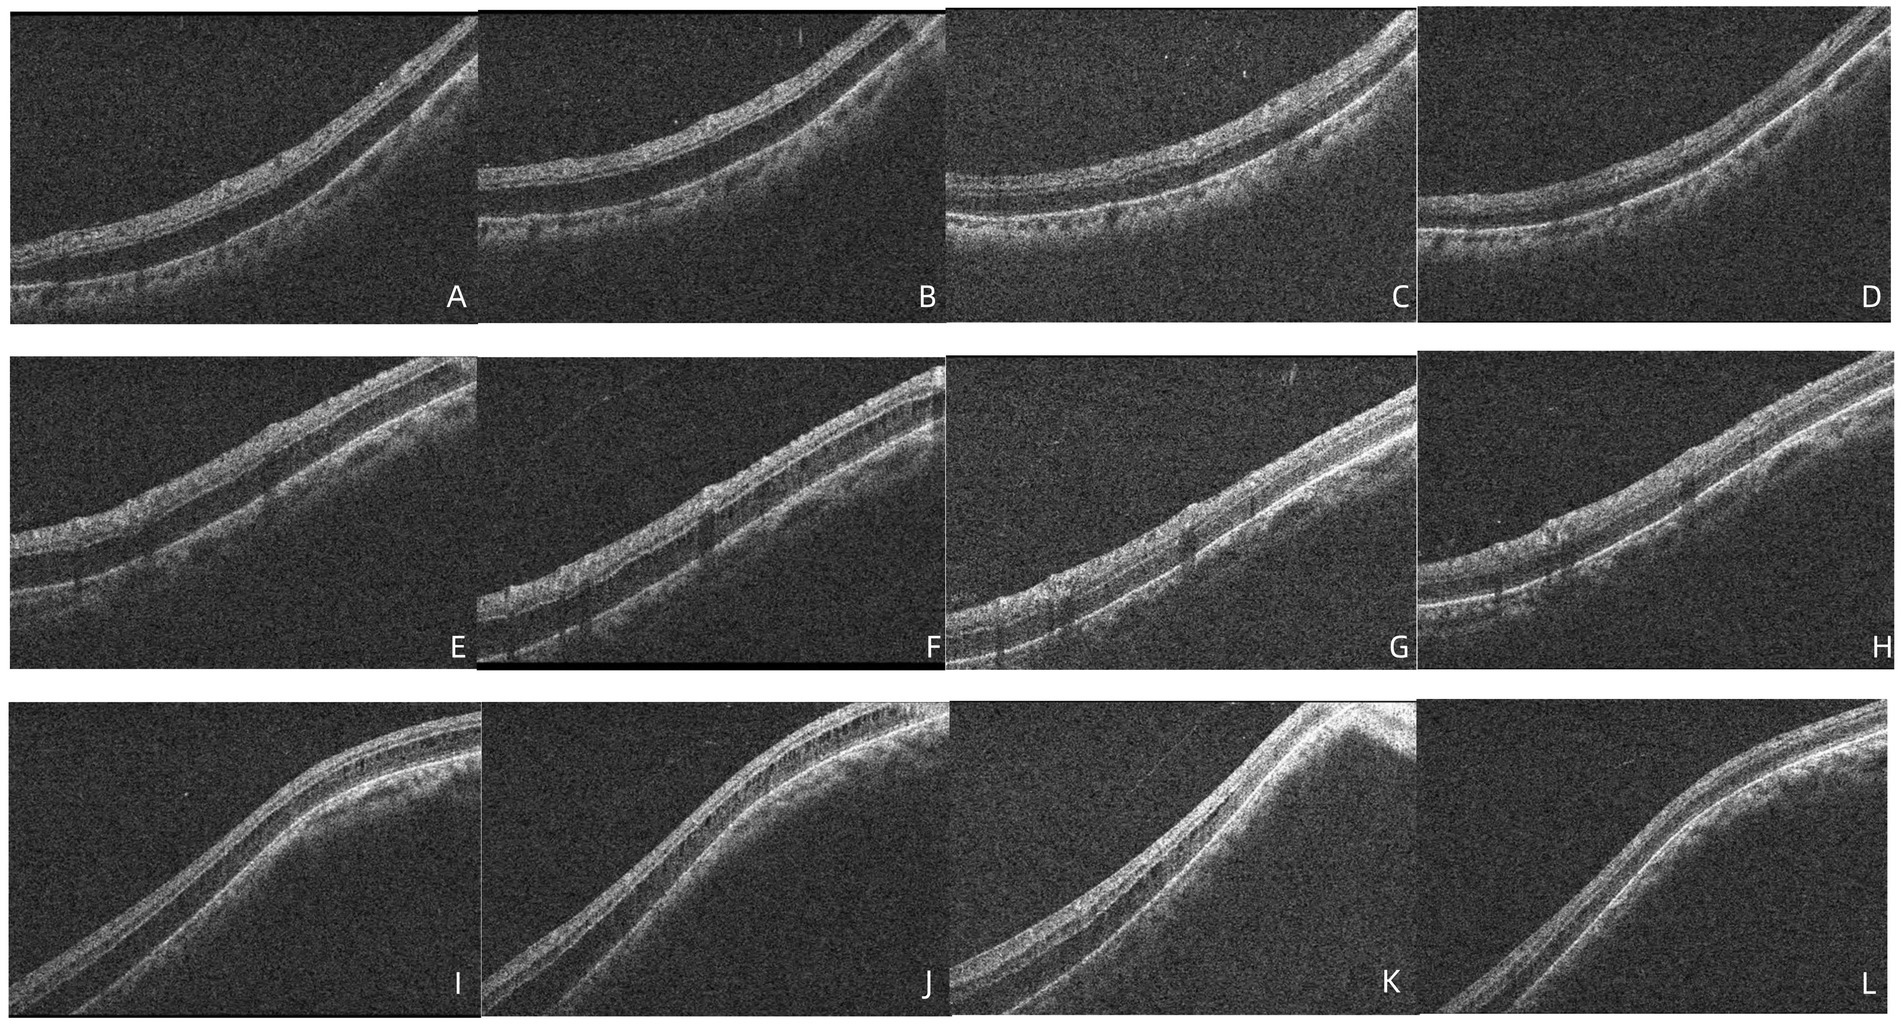

At the time of the patient’s visit, the axial length was 25.33 mm in the right eye and 25.16 mm in the left eye; his axial length 1 month ago was 25.24 mm in the right eye and 25.14 mm in the left eye. There was no significant difference in axial length between them. The corneal curvatures of the right and left eyes were 44.00 and 43.25 D, respectively. Anterior segment examination was normal, and no inflammatory cells were observed in the anterior chamber or vitreous of the left eye. B-ultrasonography revealed no vitreoretinal traction. Optical coherence tomography (OCT) demonstrated retinal splitting in the macular area, on the temporal side of the macula, and near the superior and inferior vascular arches, occurring in the outer plexiform layer without a macular hole, VMT, or macular epiretinal membrane (ERM) (Figure 1). Fluorescein and indocyanine green angiography revealed no capillary leakage in the macula or optic disc (Figure 2). There were no obvious abnormalities in the binocular visual field. Although no active inflammation was present in the left eye, the patient was given empirical therapy including oral prednisolone at 60 mg/day for 1 week, followed by 50 mg/day for 1 week. Steroid eye drops were prescribed as well. After this 2-week treatment, OCT showed that the retinoschisis had become aggravated, and the best-corrected visual acuity had decreased to 20/66 (Figures 3A,B and Figures 4A,B,E,F,I,J).

Figure 1. OCT images showed the retinoschisis. (A) The splitting of the outer plexiform layer in the macula, with a complete PVD, lack of vitreomacular traction, or epiretinal membrane. (B) The retinoschisis near the superior vascular arch. (C) The retinoschisis near the inferior vascular arch. (D) The retinoschisis in the temporal side of the macula.